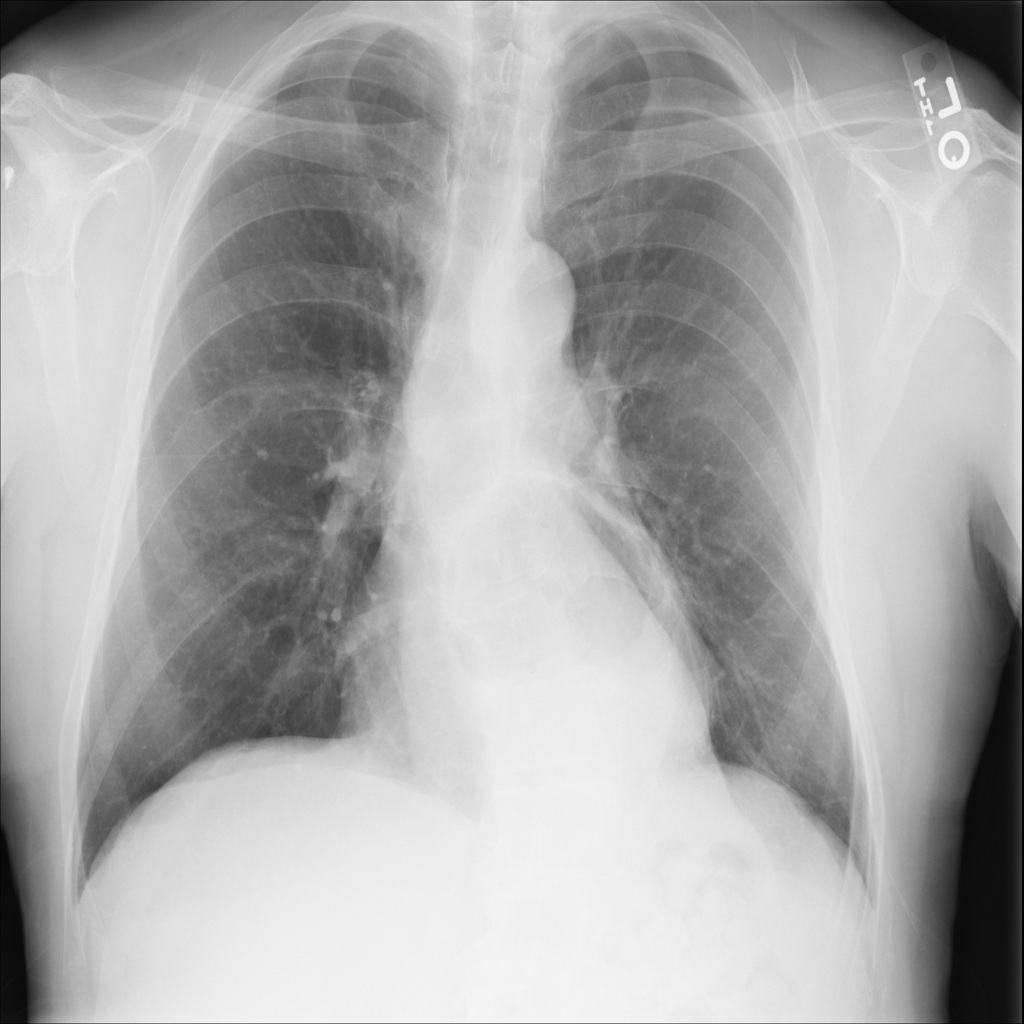

Showing up to 90 reference images for Hernia.

PAT-4F7E · IMG-000Hernia

PAT-4F7E · IMG-000

PA